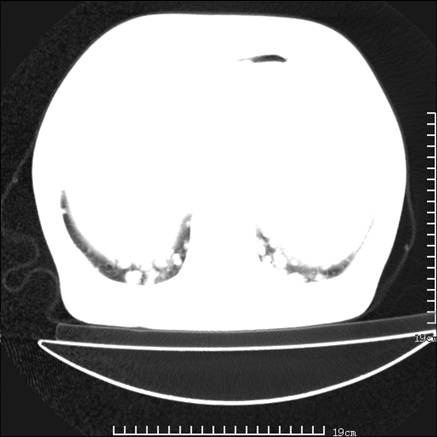

张男,75岁,干咳半年余,小便不利二年,b超检查前列腺增大,未见明显肿块;前列腺癌血生化检查多项指标明显增高。

双肺内多发转移瘤,纵膈淋巴结转移。来源前列腺?建议盆腔mri进一步检查。

双肺转移满了。

两肺广泛转移瘤。